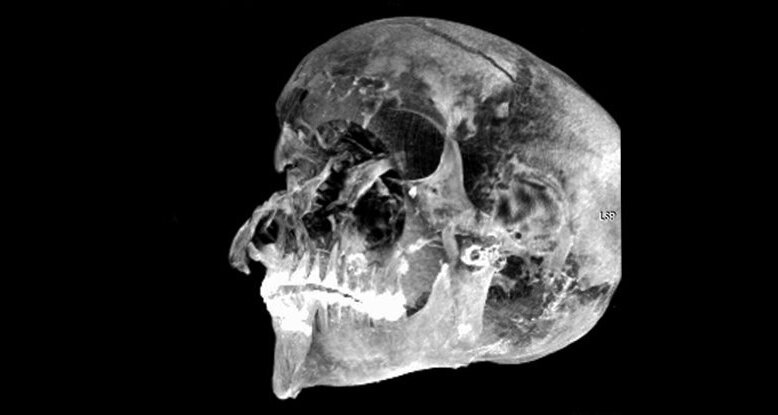

Секененра Таа II был известен как «Храбрый» и правил южным Египтом в течение относительно короткого периода, примерно с 1558 по 1553 год до нашей эры. Его правление внезапно закончилось, когда он встретил жестокую насильственную смерть. Исследователи из Каирского университета и Министерства древностей Египта использовали современные методы визуализации, чтобы выявить новые подробности этого странного происшествия.

Останки Секененра были впервые обнаружены в 1881 году, а обследования в 1886 и 1906 годах показали, что при жизни он получил серьезные травмы головы. В 1960-х рентгеновские снимки выявили пять отдельных травм на его черепе, но нигде больше. Вдобавок ко всему его бальзамирование, казалось, было произведено очень наспех. Как ни странно, для сохранения тела не использовались соли, мозг оставался на месте, а в черепе не было ткани.